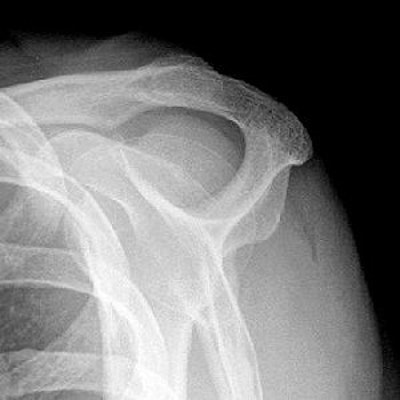

![]() |

| Mathematic determination of acromial shape. Then on parasagittal T2-weighted MR image, angle between anterior third and posterior two-thirds is measured. In this case, the anterior angle of deflection is 180° - 168° = 12°, indicating slightly curved (type 2) acromion in S-2 position. |